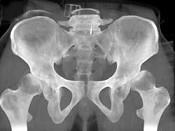

问题 男,23岁,跛行,外展受限,两下肢不等长,结合图像,最可能的诊断是?(?)

选项 A.髋关节中心脱位 B.髋关节后脱位 C.髋关节前脱位 D.先天性髋内翻 E.髋关节结核

答案 B